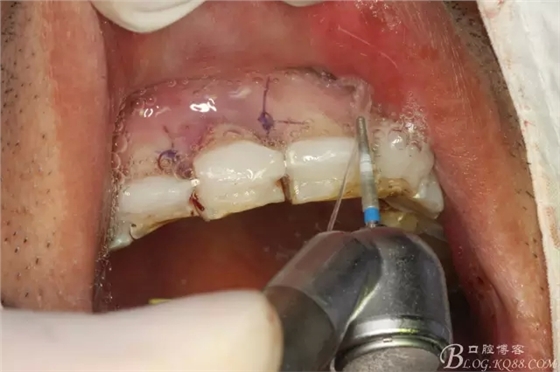

圖8.預(yù)備11根尖3mm。并MTA倒充填

圖12.全酸蝕要粘結(jié)的牙面。并縫合11兩側(cè)牙齦。